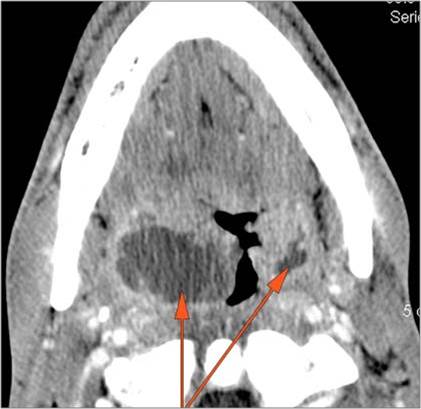

9 month old male presenting to the emergency room with poor feeding, fever, respiratory distress and possible retropharyngeal abscess or suppurative retropharyngeal adenitis.Exam

There is reactive retropharyngeal lymphadenopathy. |

There is suppurative retropharyngeal lymphadenopathy. |

Yes | NA |

If there is suppurative retropharyngeal adenopathy what is the maximum short axis dimension of the largest suppurative node. Measurement |

< 2cm | NA |

Pharyngitis with suppurative retropharyngeal adenitis.